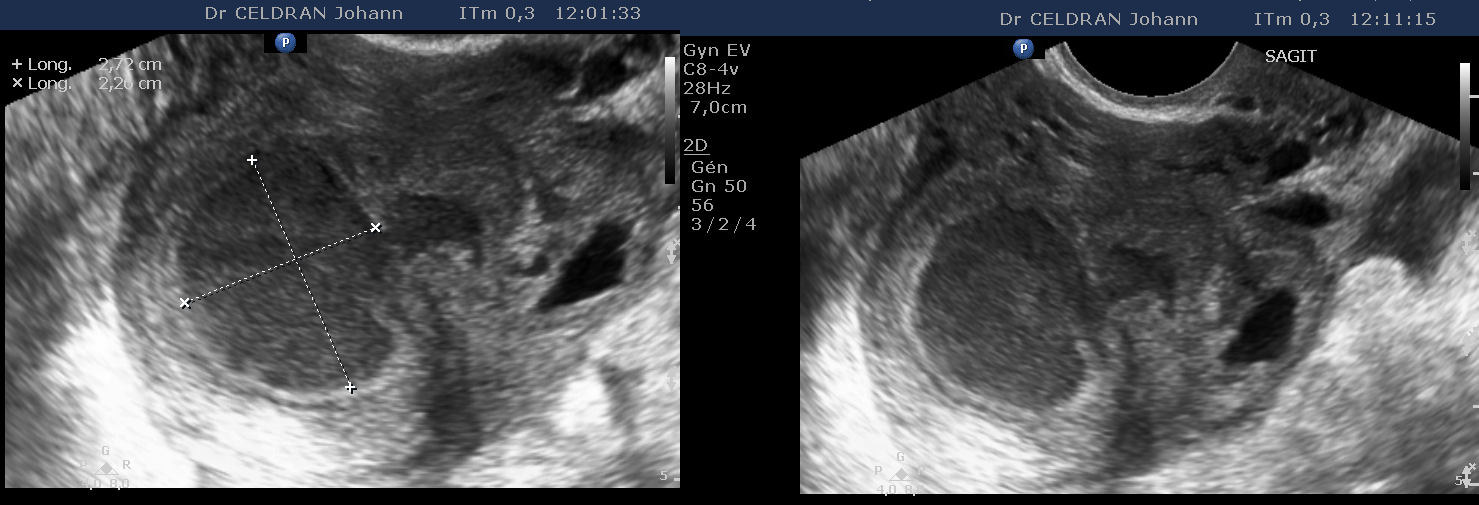

Celle d’un abcès tubo-ovarien (pyosalpinx) droit.

Tableau ciinique de douleur de la fosse iliaque droite avec syndrome infectieux clinique et biologique chez une patiente traitée pour endométrite sur stérilet depuis une 15aine de jours.

L'examen de l'ovaire droit met en évidence la présence d'une formation liquidienne intra-ovarienne mesurant près de 30mm de grand axe, uniloculaire, à contenu finement échogène que l'on parvient à mobiliser à la pression de la sonde et à faire partiellement sourdre dans ce qui semble correspondre la portion toute proximale de la trompe.

Le tissu ovarien entourant cette image liquidienne parait ici épaissi et refoulé, sans follicules échodécelable.